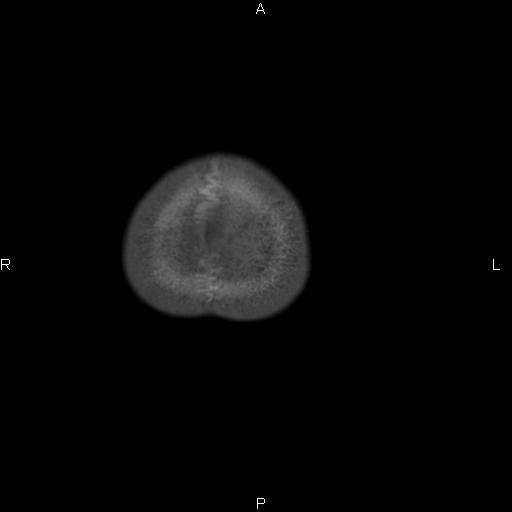

标题: CT27115:大家看一看,这孩子的颅骨表现? [打印本页]

标题: CT27115:大家看一看,这孩子的颅骨表现?

感觉第2个颅缝密度高,额顶部板障有点厚,正常变异?地中海贫血?